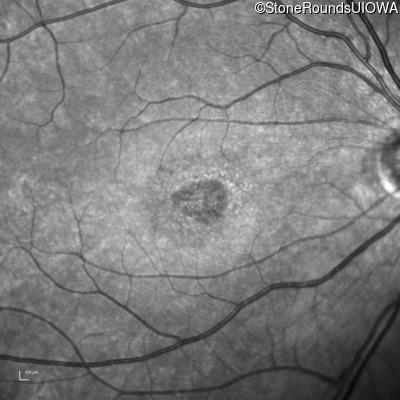

AR Stargardt Disease (IIA)

Age at visit:

15 years

OD

OS

20/125 -1

20/80

AR Stargardt Disease

ABCA4

Val256Val GTG>GTT

Gly1961Glu GGA>GAA

AR